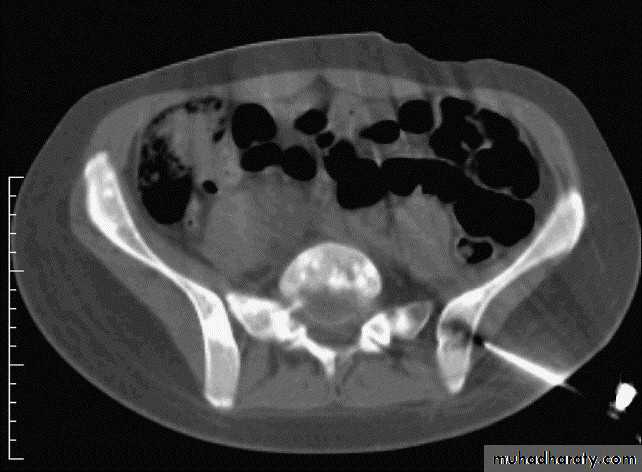

IV. computed tomography in bone disease (CT scan ) :

1.Demonestrating abnormality in the pelvis and spine2.Demonstrating the extent & characterization of bone tumour in selected cases to complement MRI

3.As gide of bone biopsy